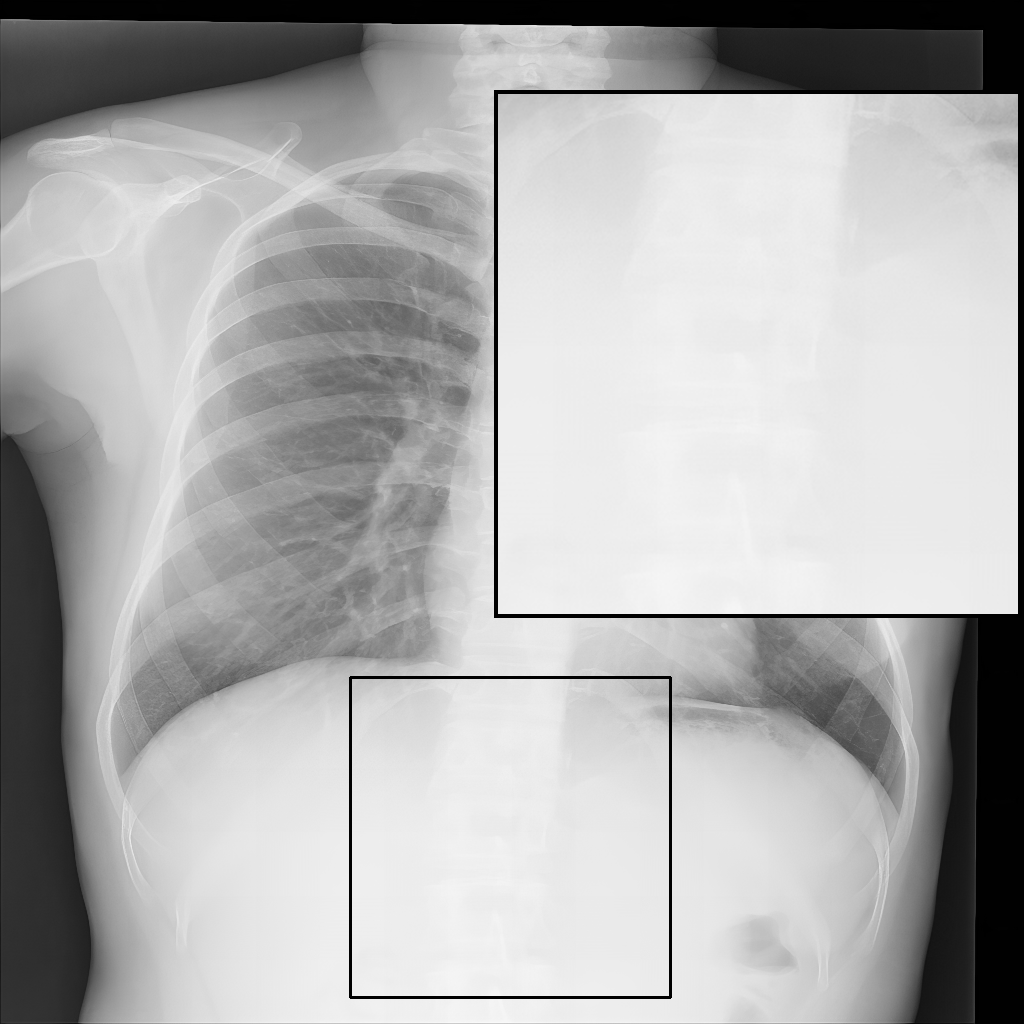

Fig. 3 shows image samples from the above datasets.

Figure 3: Image diversity across four datasets: (a) JSRT, (b) Montgomery County X-ray, (c) NIH ChestX-ray14, and (d) CheXpert